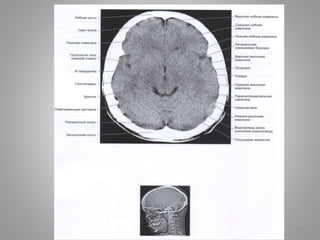

Обстурктивна некомунікативна

гідроцефалія.

• Дитина із скаргами на головний біль вранці.

• Отримані зображення

• Помітне розширення III і бічних шлуночків на Т2-

зважених зображеннях (110 А, В). На сагітальному

знімку в режимі Т1 (110С) видно розтягнутий III

щлуночок і нормальний за розміром IV шлуночок.

• Крім того, є очевидний стеноз або оклюзія сільвієвого

водопроводу.

• Крім того, є очевидний стеноз або оклюзія

сільвієвого водопроводу.